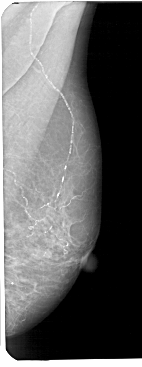

A_1191_1.LEFT_CC

LEFT_CC LINES 5071 PIXELS_PER_LINE 2356 BITS_PER_PIXEL 12 RESOLUTION 43.5 OVERLAY

FILE: A_1191_1.LEFT_CC.OVERLAY

TOTAL_ABNORMALITIES 1

ABNORMALITY 1

LESION_TYPE CALCIFICATION TYPE PLEOMORPHIC DISTRIBUTION LINEAR

ASSESSMENT 4

SUBTLETY 2

PATHOLOGY MALIGNANT

TOTAL_OUTLINES 1

BOUNDARY